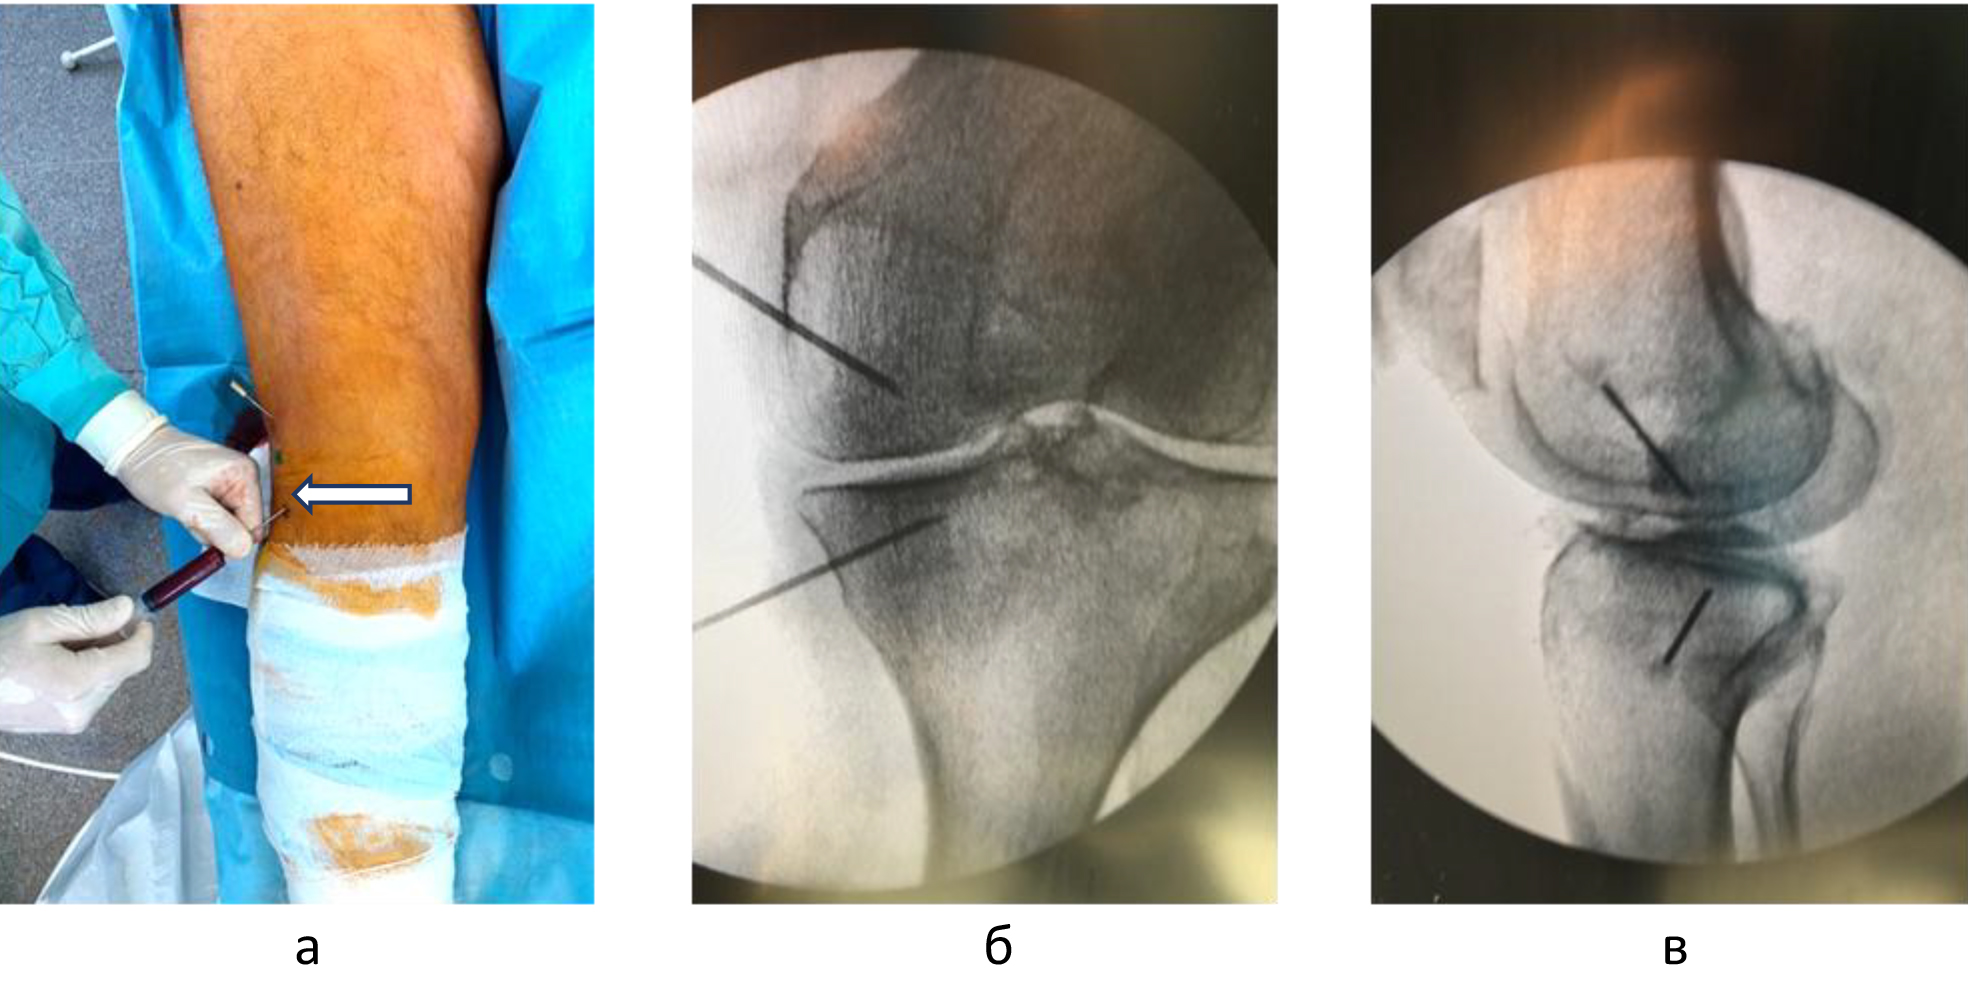

Для определения локализации и распространенности перегрузочного отека костного мозга всем пациентам выполняли МРТ. На Т1-взвешенных изображениях визуализировали снижение интенсивности сигнала, на Т2-взвешенных изображениях с жироподавлением и на коротких последовательностях «восстановления – инверсии» (STIR) выявляли высокую интенсивность сигнала (рис. 1).

Техника подготовки препарата и инъекции. Забор крови и приготовление ОТП выполняли в условиях процедурного кабинета или перевязочной при соблюдении необходимых правил асептики и антисептики. Согласно методике YCELLBIO PRP (Корея), двухкратно центрифугировали кровь пациента и получали 3 мл ОТП, которую центрировали в узком перешейке пробирки и забирали при помощи шприца (рис. 2) Количество тромбоцитов в готовом препарате составляло 962 ± 40 × 109/л.

Внутрикостные инъекции ККМ и ОТП выполняли в условиях операционной. Используя 2%-й раствор лидокаина, инфильтрировали мягкие ткани по внутренней или наружной поверхности коленного сустава на 2 см проксимальнее и на 2 см дистальнее уровня суставной щели. Троакары вводили в кость вкручивающими движениями под углом 45 градусов по отношению к оси конечности и продвигали на глубину 1,5 см, достигнув субхондральных структур. Позиционирование троакаров оценивали с помощь электронно-оптического преобразователя (ЭОП) в 2 стандартных проекциях (рис. 3).

Объективным показателем регресса болевого синдрома и нормализации клеточного метаболизма субхондральных структур являлось значительное сокращение объема или вовсе исчезновение зон трабекулярного отека костного мозга, что подтверждалось уменьшением гиперинтенсивных участков по данным МРТ (рис. 4) [8].